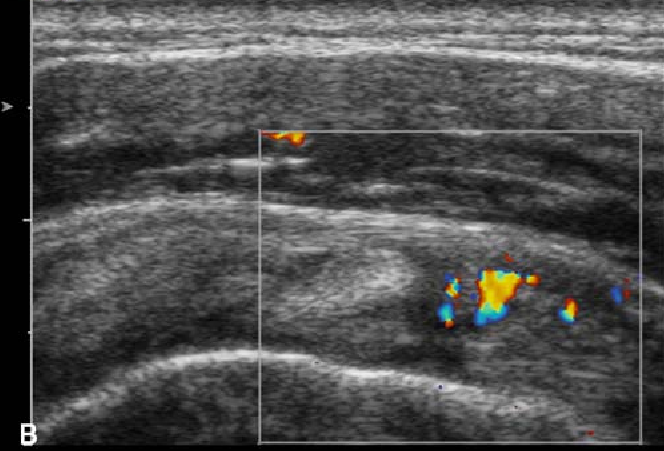

초음파상

비대된 인대가 관찰되고,

도플러 신호가 활성화되었으며,

관절낭이 부어있다면

도침치료**가 아주 효과적입니다.